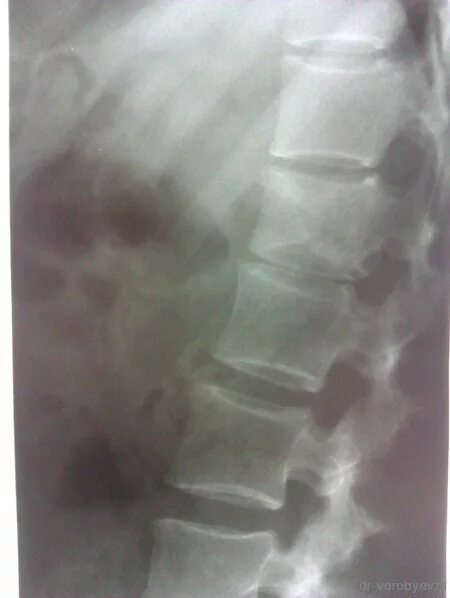

Метастазы в поясничном отделе симптомы